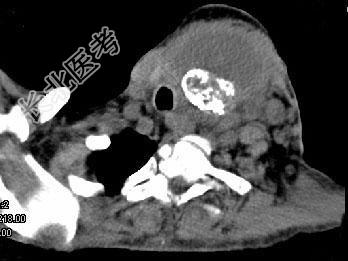

- 单项选择题女,64岁, 发现双甲状腺肿大1个月余,CT如图所示, 最可能的诊断是 ( )

A、结节性甲状腺肿

B、甲状腺腺瘤

C、甲状腺癌并淋巴结转移

D、甲状腺转移瘤

E、甲状腺结核